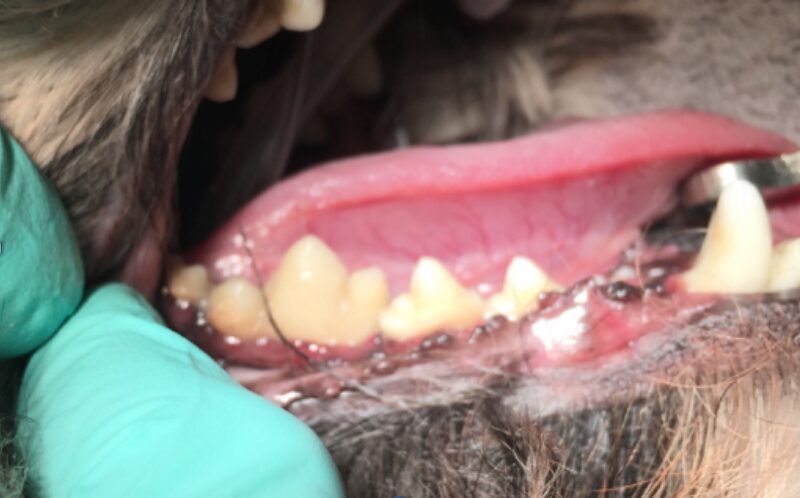

Als ich bei Leila ins Maul schaute, staunte ich schon nicht schlecht. Ich sah die Besitzerin an und fragte: „Wie alt war Leila noch mal?“ Leila war tatsächlich erst drei Jahre alt und doch wusste ich da schon, dass wir wahrscheinlich keinen Zahn retten könnten. Man sieht es wirklich nur, wenn man etwas genauer hinschaut: Leilas Zahnhälse lagen alle frei, und eitrige Beläge kamen aus der Tiefe des Zahnfachs (Abb. 2 - 5).

In Narkose sah man auf Leilas Röntgenbildern dann das gesamte Ausmaß ihrer Zahnerkrankung. Bis auf die Canini wiesen alle Zähne hochgradige Wurzelentzündungen mit Osteolysen des Kieferknochens auf. Deshalb konnte man auch schon von außen die Zahnhälse freiliegend sehen. Im Wurzelbereich waren die Veränderungen so schlimm, dass der Unterkiefer kurz vor einer Fraktur stand.

Solche Veränderungen treten oft bei einer hochgradigen Parodontitis auf. Eine Parodontitis ist die Entzündung des gesamten Zahnhalteapparates (also des Kieferknochens, des Zements, der Paradontalfasern und des Zahnfleischs) und wird durch die Bakterien, welche im Plaque enthalten sind, hervorgerufen. Diese zerstören die Anheftung der Gingiva am Zahn, und die Bakterien können bis zur Wurzel vordringen. Hier rufen sie Entzündungsreaktionen des Kieferknochens und der Gingiva hervor, wodurch beide sich zurückziehen und tiefe Paradontaltaschen entstehen lassen. Doch Leila hatte, wie auf den Bildern schön zu sehen ist, kaum Zahnstein oder Plaque.